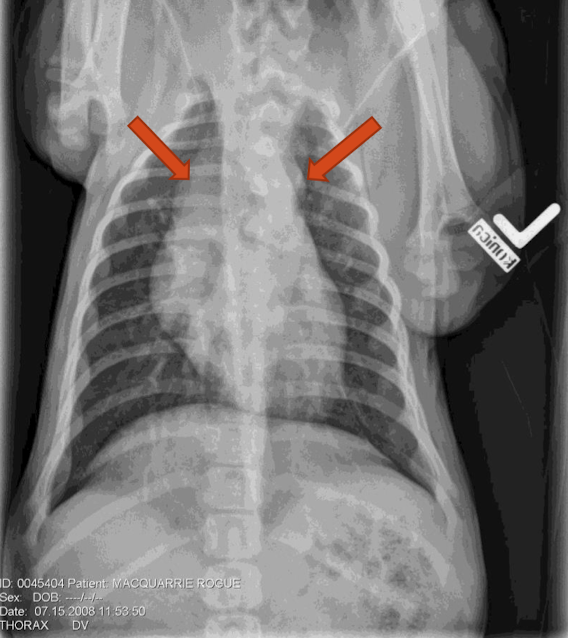

What lung pattern? What are the arrows pointing to?

Bronchial pattern

tram tracks